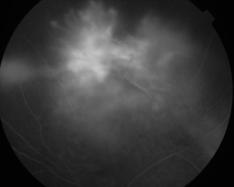

IM000031.jpg